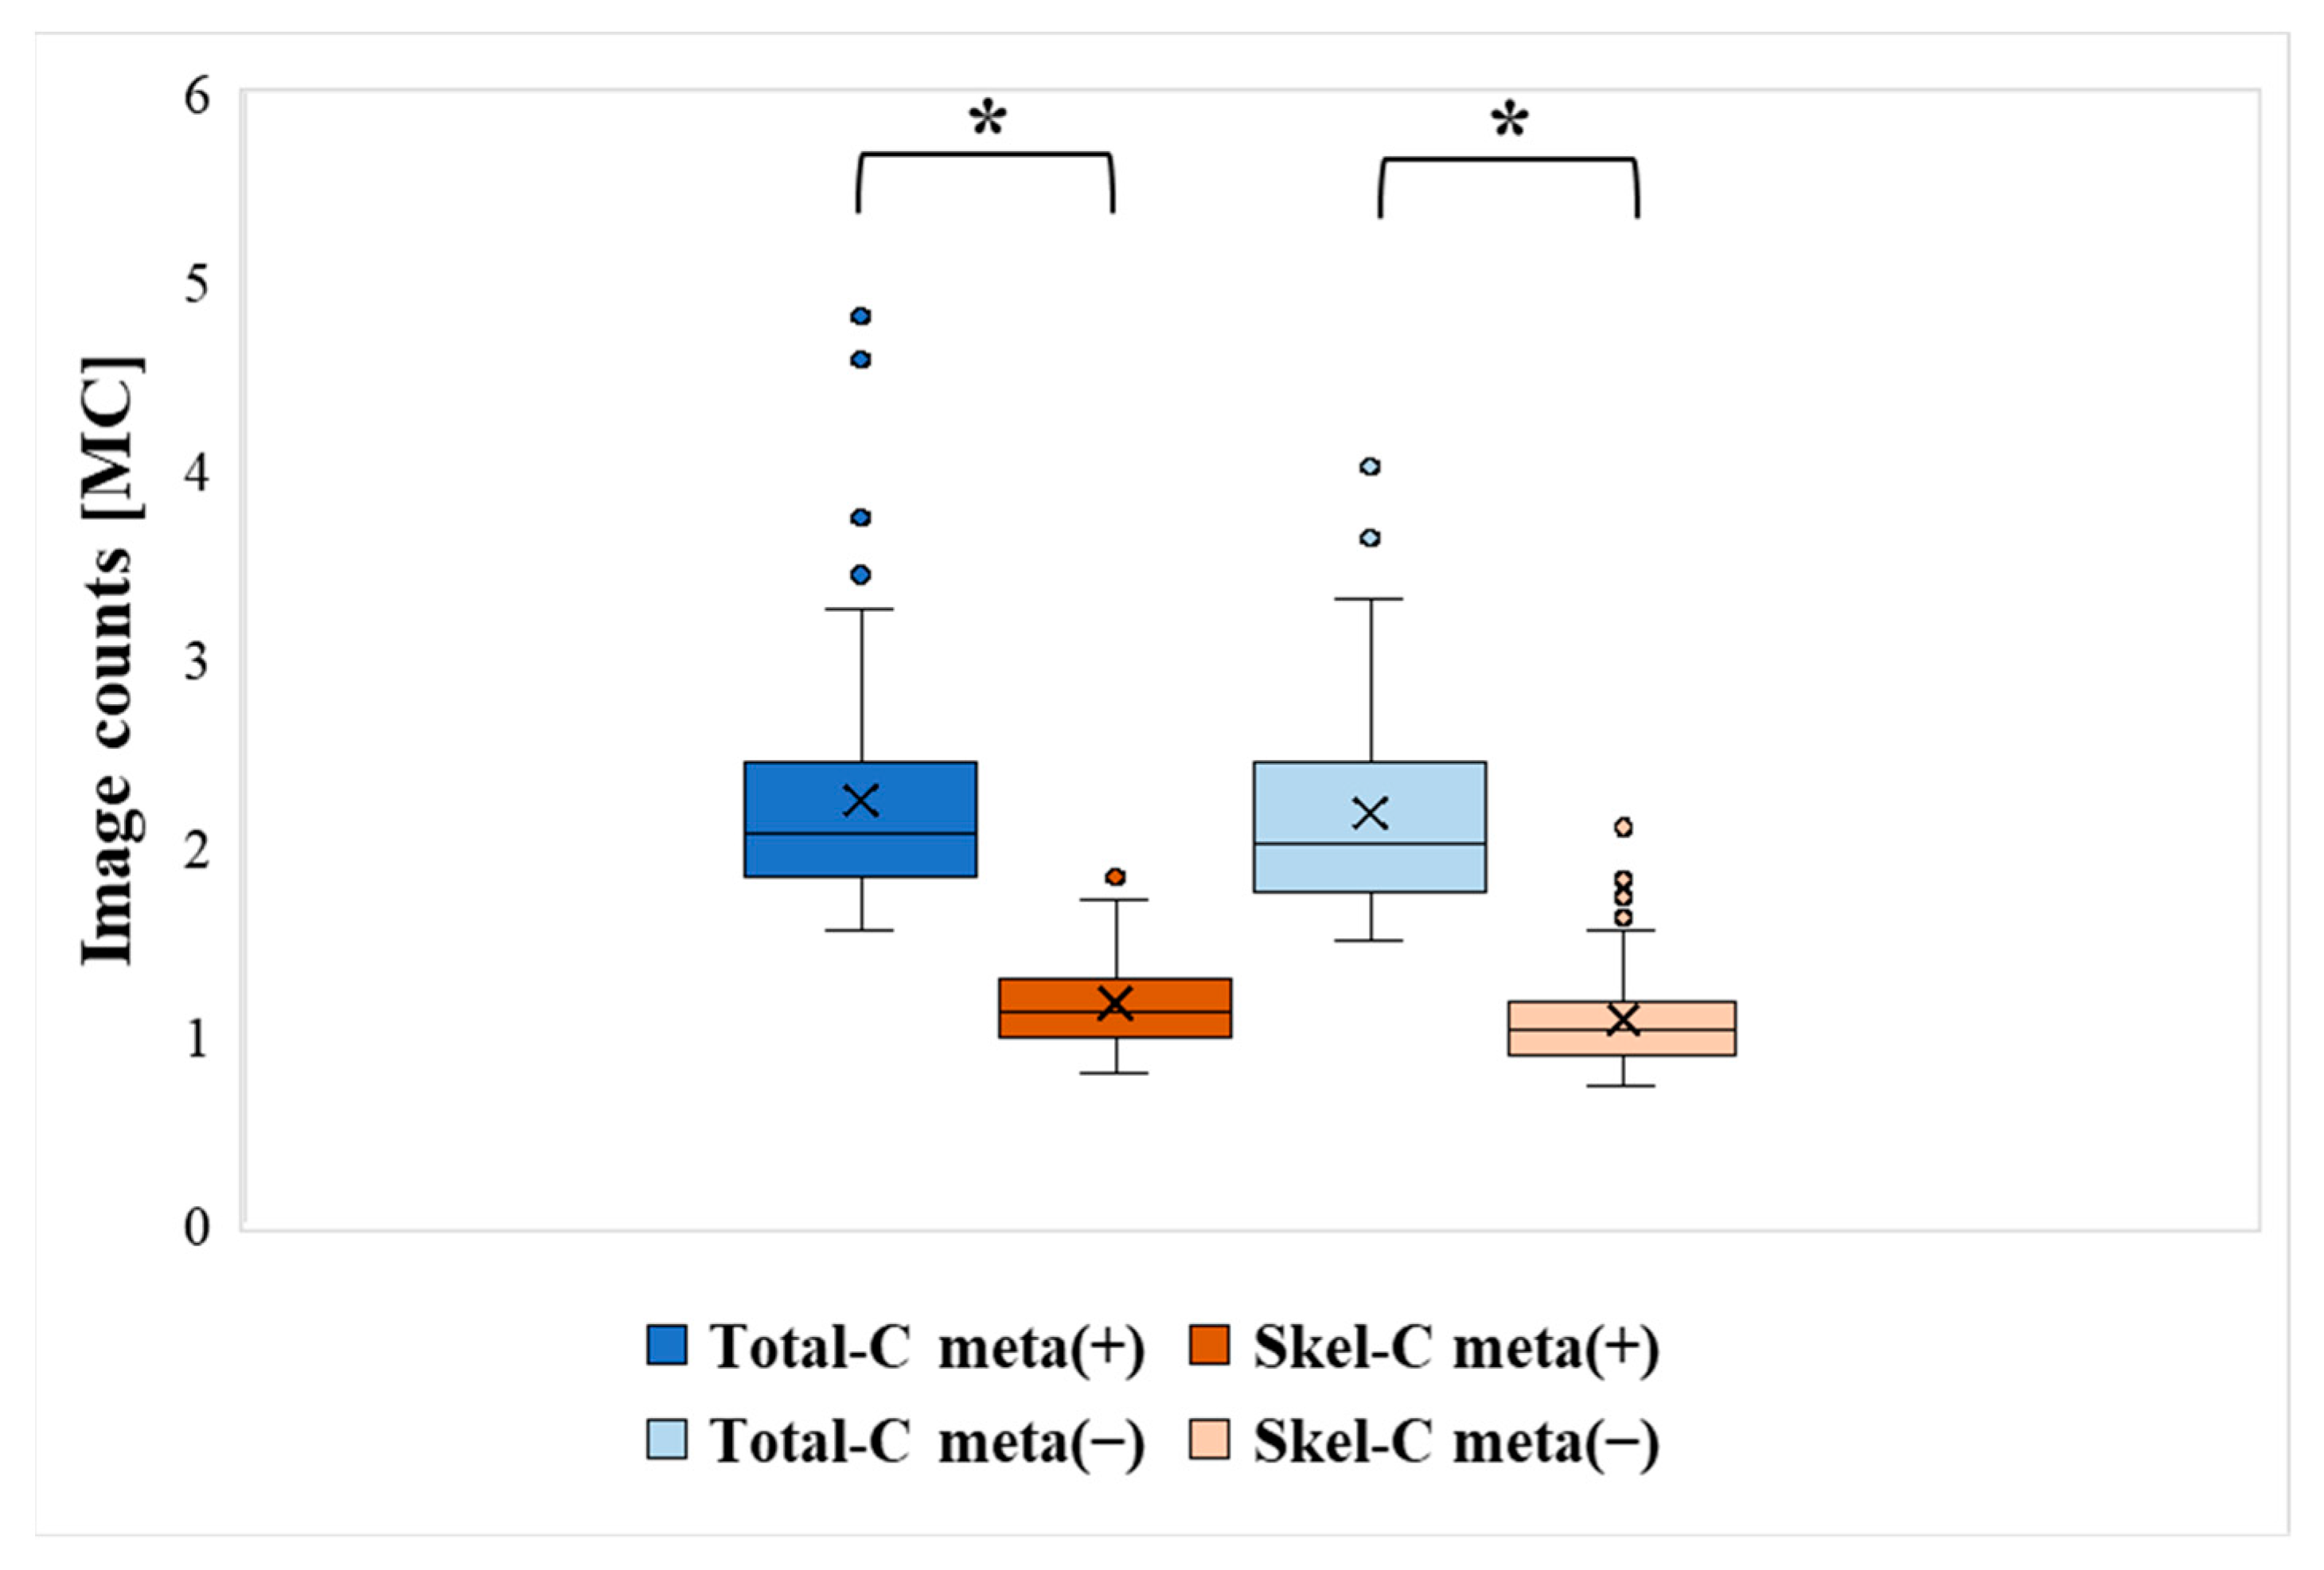

3. Results

| Bone Meta (+) | Bone Meta (−) | |||

|---|---|---|---|---|

| Total-C | Skel-C | Total-C | Skel-C | |

| Mean [MC] | 2.25 | 1.18 | 2.18 | 1.09 |

| Median [MC] | 2.07 | 1.13 | 2.02 | 1.03 |

| Min [MC] | 1.56 | 0.81 | 1.51 | 0.73 |

| Max [MC] | 4.82 | 1.85 | 4.11 | 2.14 |

| SD | 0.63 | 0.23 | 0.54 | 0.26 |